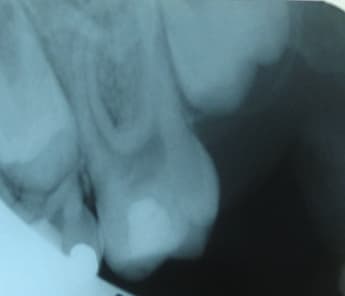

Je viens d'en récupérer une sur une 36 chez un nouveau patient de 30 ans, pan lingual cassé cet été, canaux totalement calcifiés, j'arrive pas à passer, aucune lumière (je sais je n'en suis pas une non plus hélas...). Que faire?

sur la 36 du trentenaire,j'arrêterais tout avant les faux canaux:de plus il ne semble pas y avoir de pb apicaux?

2-La 36 du trentenaire va très bien au niveau apical. J'ai besoin des canaux pour la reconstituer, je vais donc me contenter d'enlever le ciment à base d'eugénate... au risque de me voir reprocher de ne pas avoir boucher les racines "correctement". Je trouvais juste bizarre qu'il n'y ait plus de canaux, au delà de ce que j'ai appelé une pulpo ancienne (basse j'en conviens).